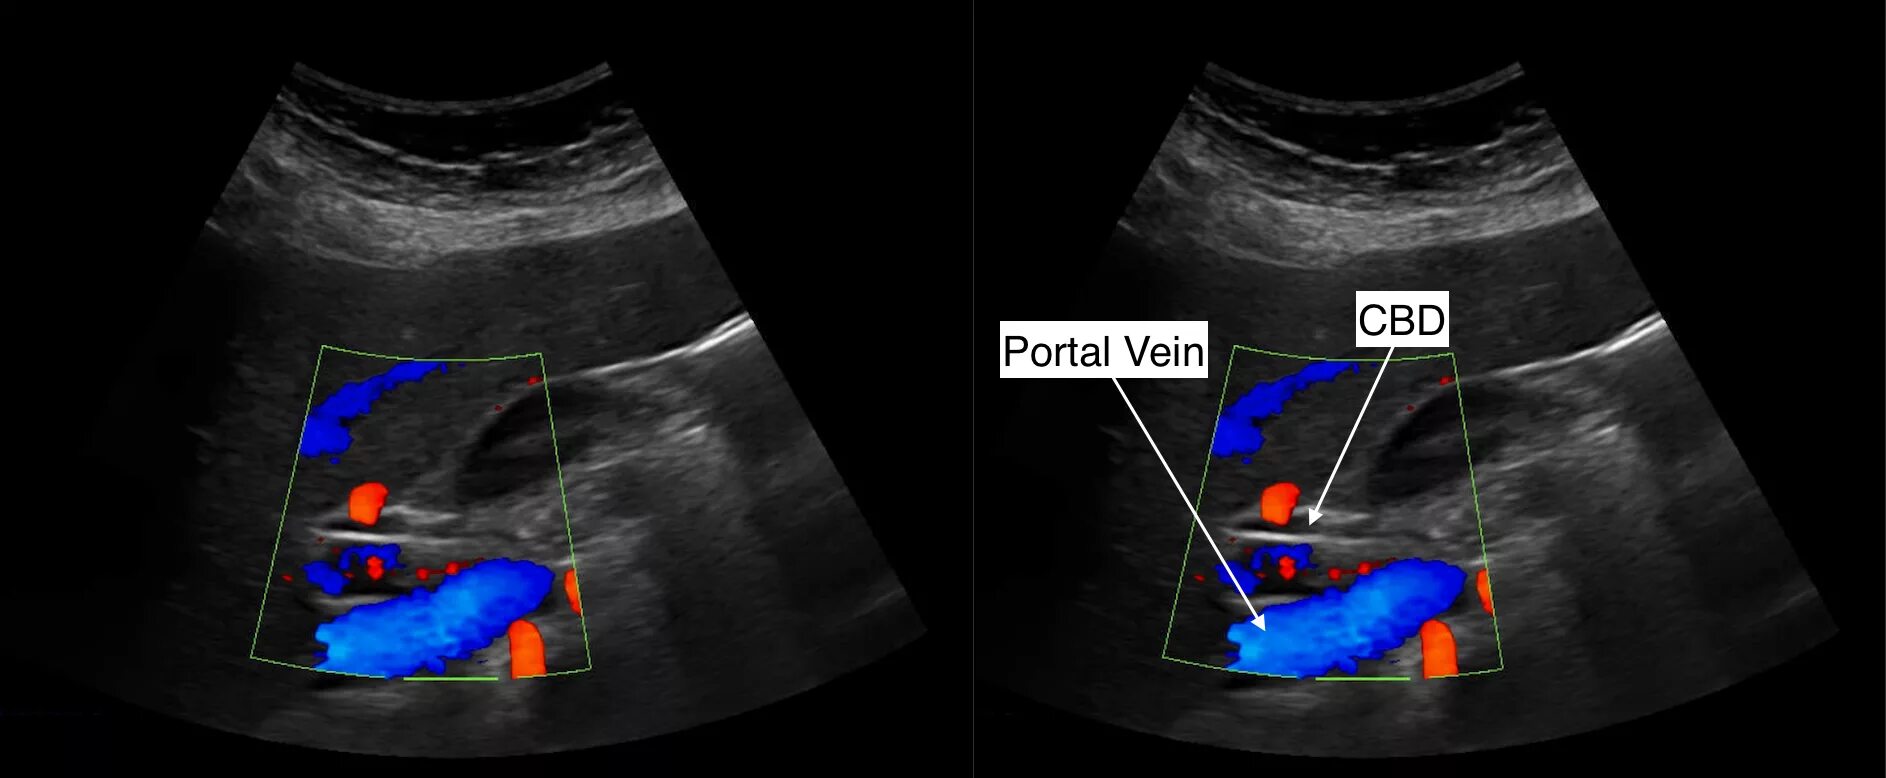

Ви и узи